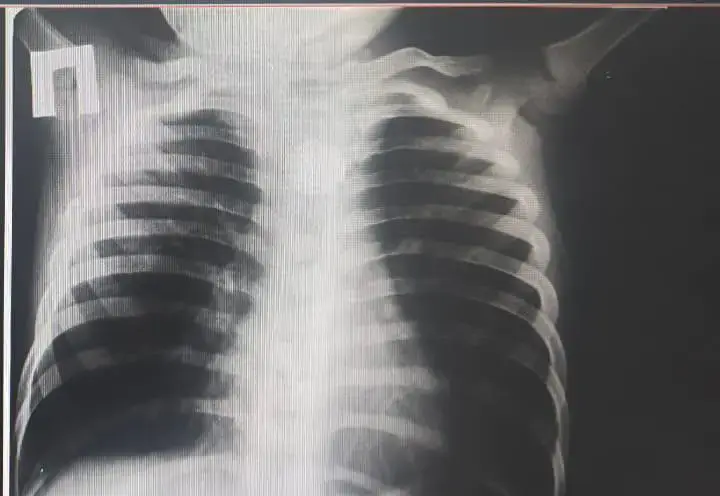

В районной больнице, где проводилось первичное обследование, рентген выявил, что в пищеводе застряла круглой формы батарейка. Это открытие потребовало немедленного вмешательства, и ребенка срочно доставили в Туркестанскую областную детскую больницу на скорой помощи.

В приемном отделении хирурги и эндоскописты провели ряд дополнительных исследований, которые подтвердили наличие инородного тела в верхней части пищевода. Врачи быстро приняли решение о проведении операции, которая, по их словам, была достаточно сложной.